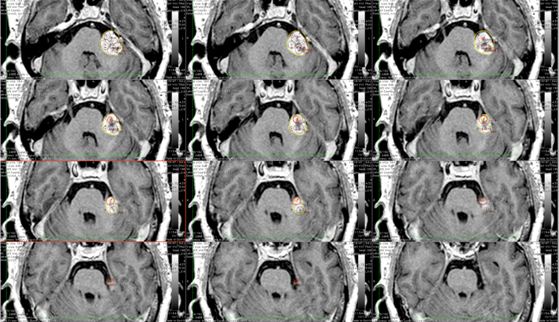

Hình 1. Hình ảnh chi tiết kế hoạch xạ phẫu bằng dao gamma quay ở ba mặt phẳng tọa độ của một bệnh nhân nữ, 64 tuổi, bị u dây thần kinh số VIII bên trái, tại Trung tâm Y học hạt nhân và Ung bướu-Bệnh viện Bạch Mai .